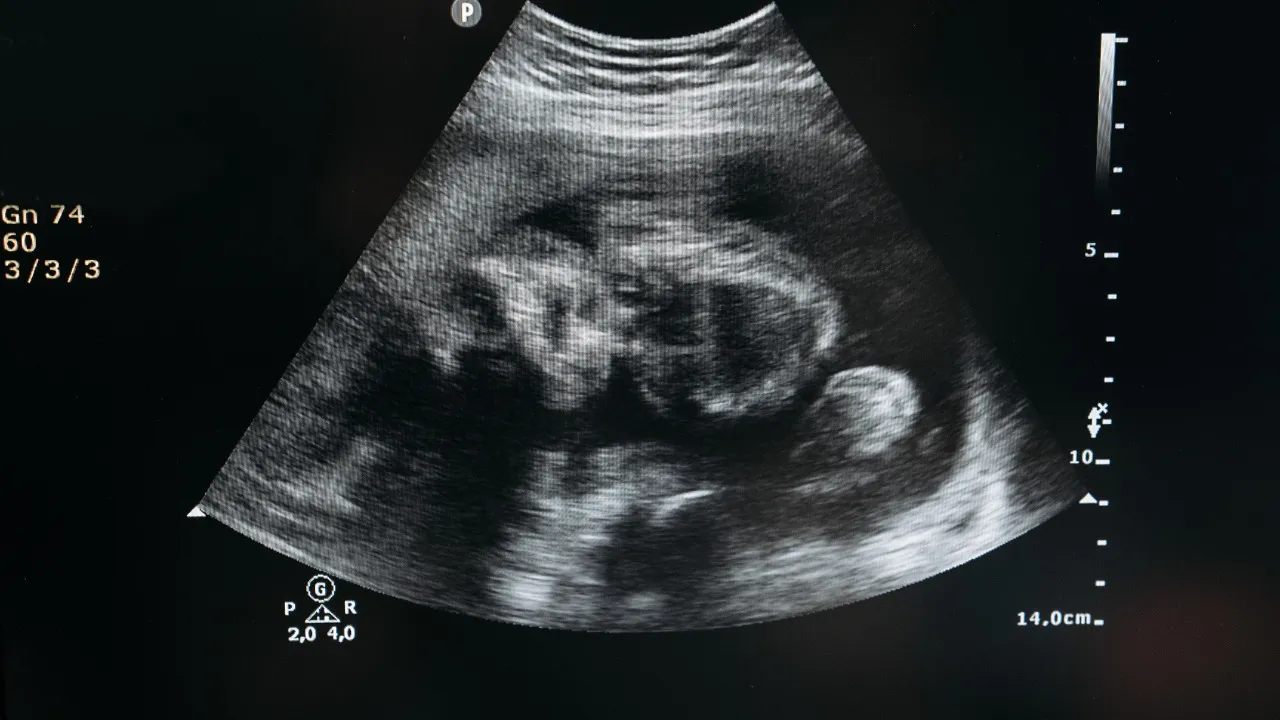

Процедура программы ЭКО с донорскими клетками предусматривает подготовку и обследование пациентки и донора. Оно включает гинекологический осмотр, УЗИ, анализы на инфекции, диагностику, которая исключает риск генетических заболеваний у донора. Затем проводится стимуляция яичников. Это помогает увеличить число половых клеток, созревших в одном цикле.